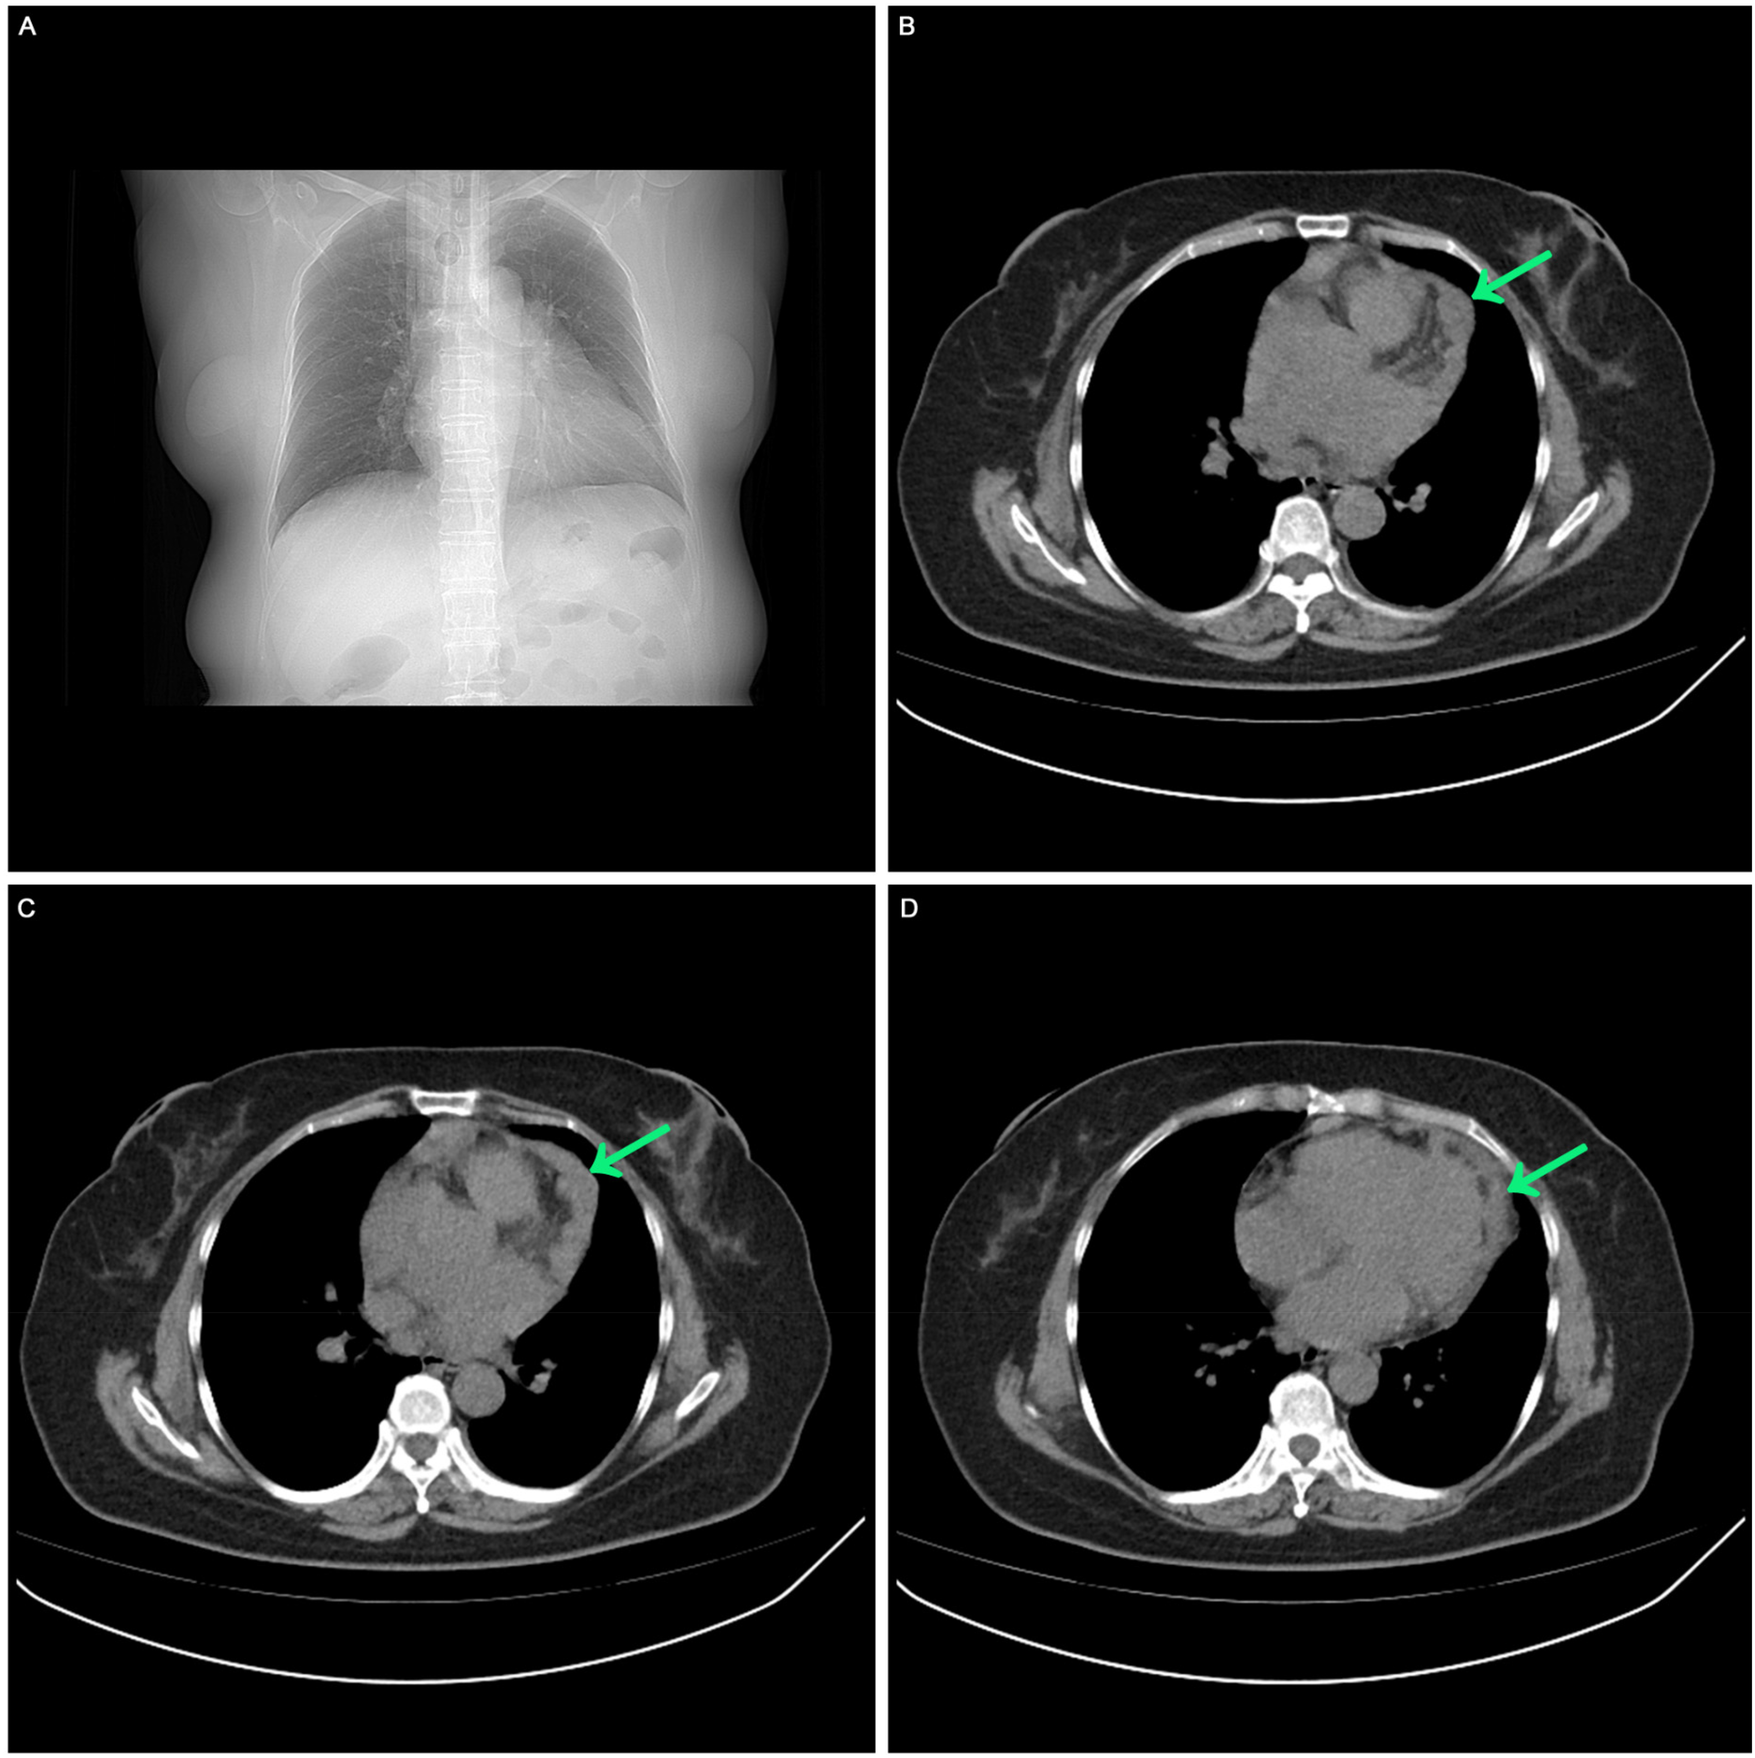

A comprehensive medical history was conducted. In May 2023, the patient sought care at our hospital's fever clinic due to “lower fever and dry cough.” Initially, a “respiratory tract infection” was suspected, and chest CT scan was performed and revealed irregular thickened pericardium (Figure 1).

Figure 1

The first visit in May 2023. (A) Chest CT scan showed no pleural effusion, no pericardial effusion. (B, C, D) Chest CT scan showed irregular low-density mass in the left side of the heart.